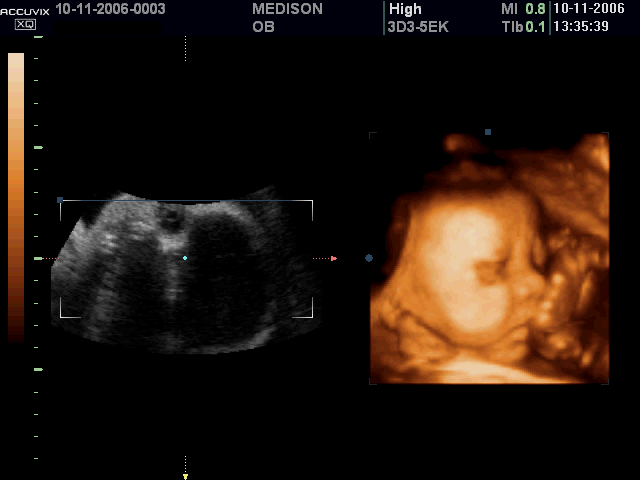

Базальное узи

Базальное узи 115 фото